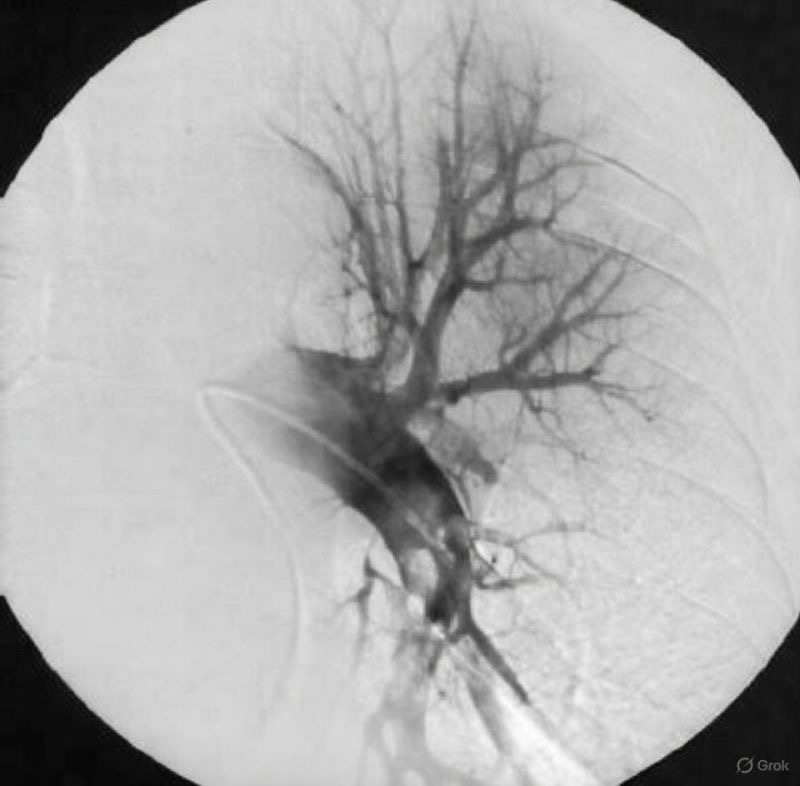

”We still tend to talk about venous thromboembolism like it’s a plumbing problem.

A blockage forms, flow is reduced, pressure builds, and treatment is about reopening the pipe.

But a thrombus isn’t an inert plug. Once it forms, it becomes biologically active.

Clot isn’t just trapped blood.

It retains active thrombin and factor Xa, becomes increasingly resistant to breakdown, and carries a significant inflammatory signal.

Even after anticoagulation is started, the clot itself can continue to drive disease.

In many ways, it behaves more like an organ than debris .

That matters when we think about embolization. When part of a thrombus travels, it doesn’t arrive downstream as a neutral obstruction.

It arrives loaded with active coagulation enzymes and inflammatory mediators. What follows isn’t just blockage, but propagation.

This helps explain why we see pulmonary embolism without an obvious DVT, why clot burden can progress early, and why timing matters so much in VTE care.

Anticoagulation is essential. It prevents new clot from forming. But it doesn’t neutralize the biologic activity of the thrombus that’s already there.

That clot can remain enzymatically active, inflammatory, and emboligenic for far longer than we tend to acknowledge.

This is where total thrombus clearance becomes important, beyond restoring flow.

Removing clot removes the thrombin reservoir, the inflammatory stimulus, and the substrate for ongoing embolization and re-thrombosis.

It’s less about cosmetics on imaging and more about biologic source control.

As we rethink how we treat VTE, the question shouldn’t only be whether flow looks better at the end of the case.

It should be whether the clot has lost its ability to cause harm.”